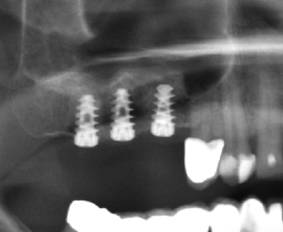

Das ist ein sehr minimal invasiver Eingriff, um die Kieferhöhlenschleimhaut bei einer unzureichender Knochenhöhe hochzuheben und die Implantate unter der Kieferhöhle setzten zu können.

Mit einem Stab (Osteom) wird die Kieferhöhle angehoben, Knochenersatzmaterial Cerabone wird unter die Kieferhöhlenschleimhaut mit

einem Stab eingeschoben.

Das Knochenersatzmaterial Firma Botiss

Cerabone

wird aus dem Rinderknochen

gemacht und mit ca. 1200 Grad im Offen

gesintert. Damit ist er gegen Prionen (BSE) sicher.

Danach werden dort Implantate eingesetzt.